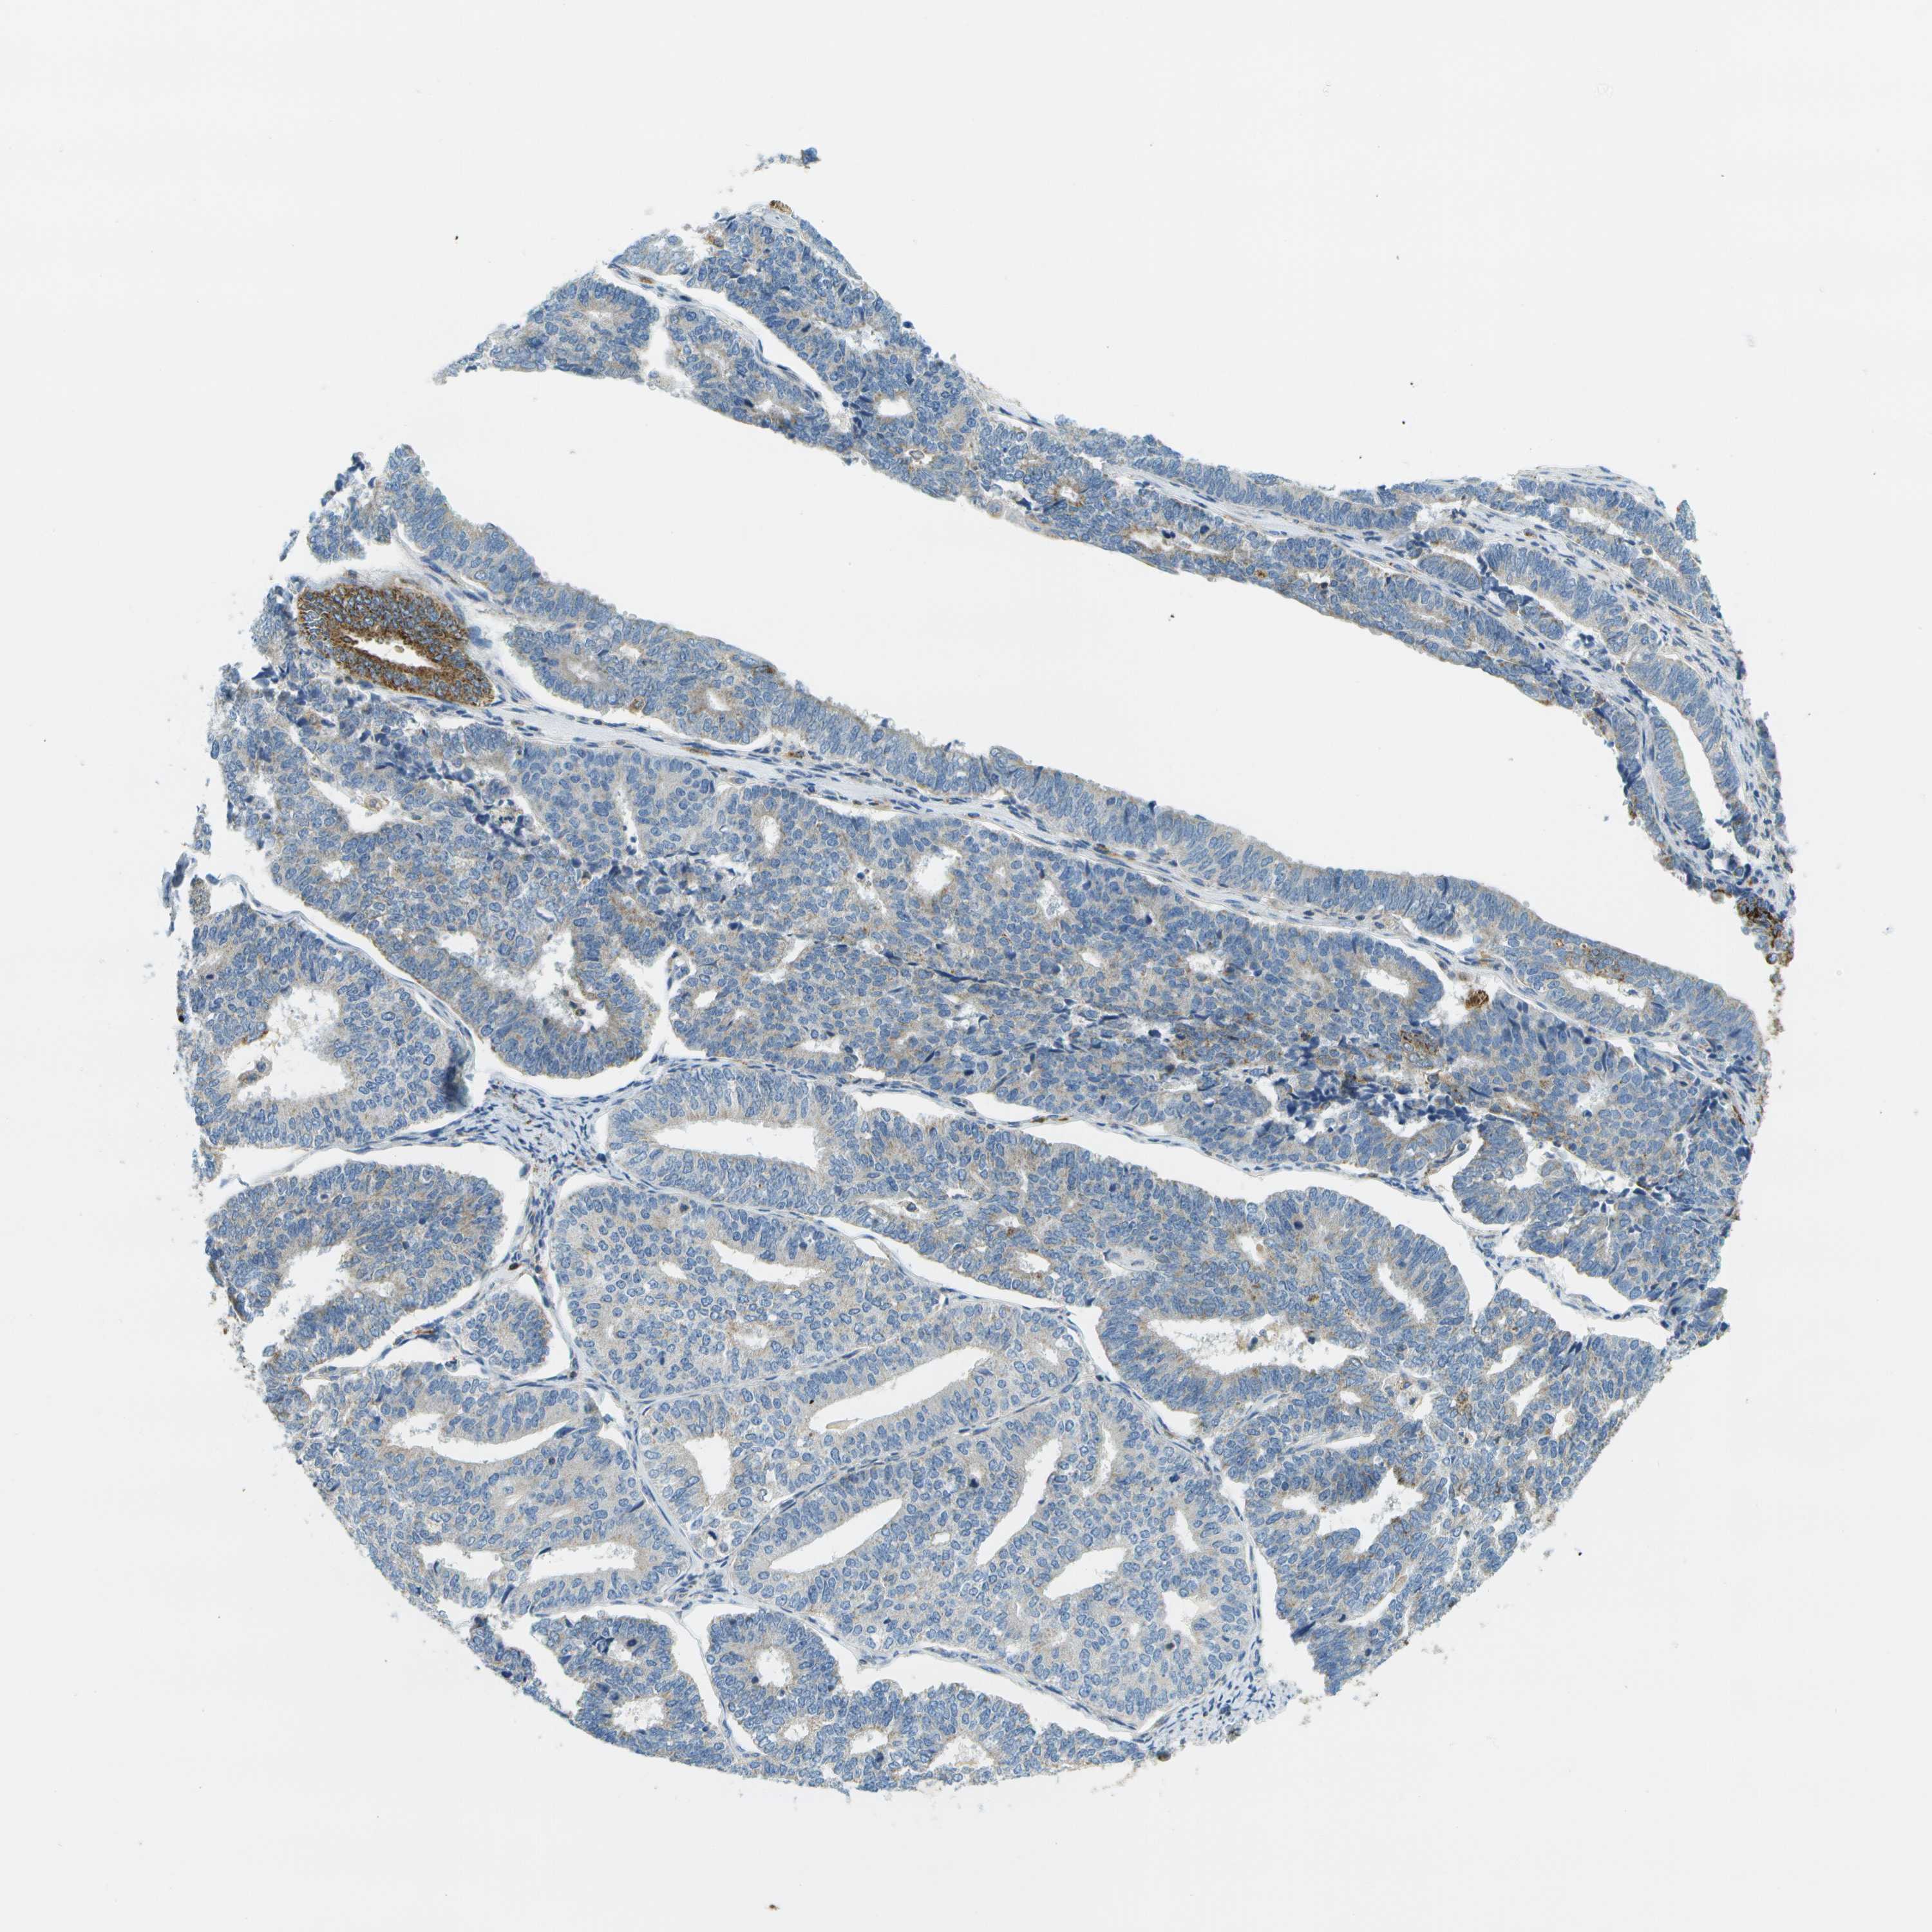

ENDOMETRIAL CANCER - Protein expressioni

A mouse-over function shows sample information and annotation data. Click on an image to view it in a full screen mode. Samples can be filtered based on level of antibody staining by selecting one or several of the following categories: high, medium, low and not detected. The assay and annotation is described here.

Note that samples used for immunohistochemistry by the Human Protein Atlas do not correspond to samples in the TCGA dataset.

Antibody stainingi

Antibody staining in the annotated cell types in the current human tissue is reported as not detected, low, medium, or high, based on conventional immunohistochemistry profiling in selected tissues. This score is based on the combination of the staining intensity and fraction of stained cells.

Each image is clickable and will lead to virtual microscopy that enables deeper exploration of all samples and also displays staining intensity scores, fraction scores and subcellular localization as well as patient and tissue information for each sample.

Antibody HPA017379

Staining

High

Medium

Low

Not detected

Intensity

Strong

Moderate

Weak

Negative

Quantity

>75%

75%-25%

<25%

None

Location

Nuclear

Cytoplasmic/membranous

Cytoplasmic/membranous,nuclear

Adenocarcinoma, NOS